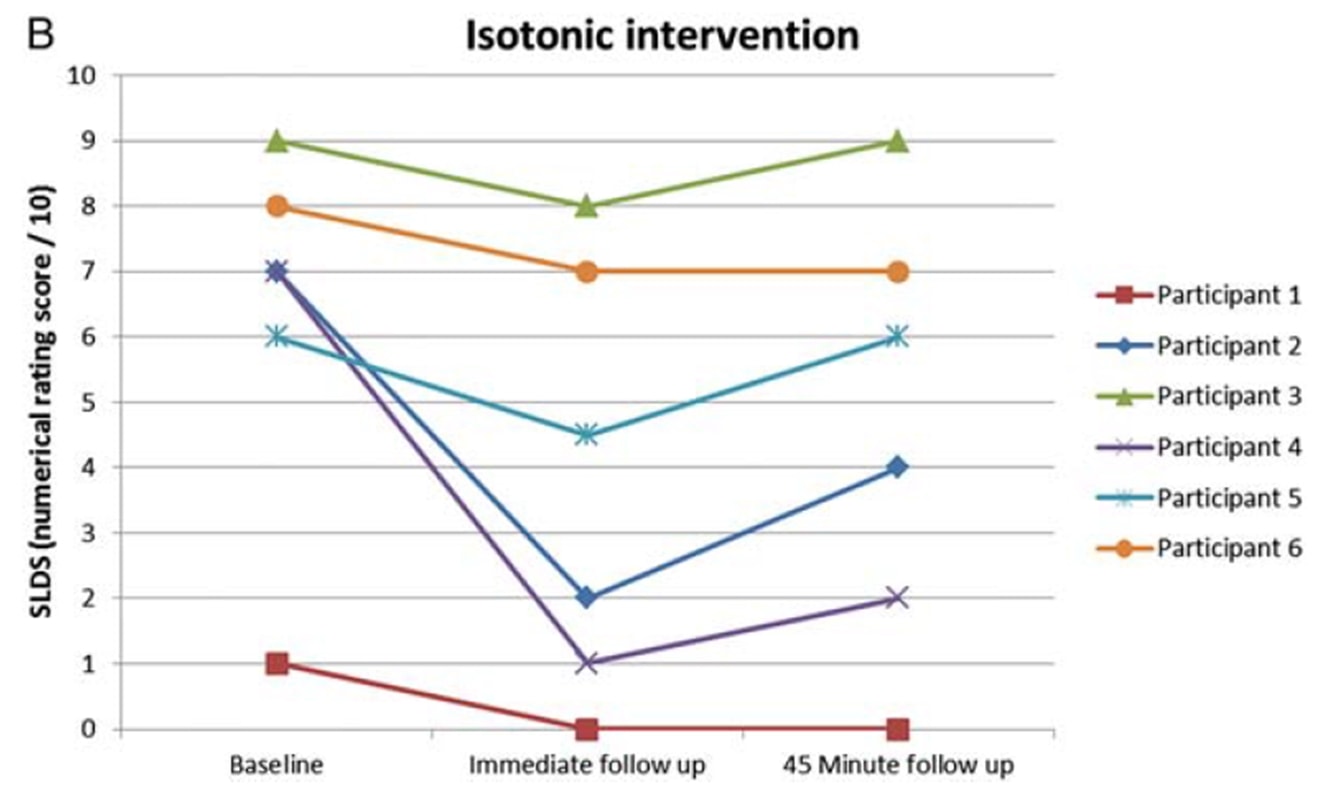

Рио и др. (2015) положили начало некоторой тенденции, когда провели перекрестное исследование на 6 волейболистах с тендинопатией надколенника. Их результаты были поразительными: у всех игроков сразу же уменьшилась боль - в среднем с 7/10 по NRS до 0, и только один из 6 человек сообщил, что после изометрических сокращений боль оставалась на уровне 1- в течение как минимум 45 минут. Протокол, который они использовали, состоял из 5 сетов с 45-секундным сокращением в тренажере для разгибания ног и усилием в 70% от максимального добровольного усилия. Они также обнаружили, что изометрия способна уменьшить торможение коры головного мозга и увеличить силу на 19%. Они сравнили изометрическое вмешательство с изотоническим, и эффекты, наблюдаемые в изометрической группе, не могли быть достигнуты в изотонической группе: